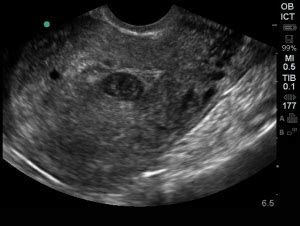

Hey everyone, let’s dive into something super important that can pop up during early pregnancy – the pseudogestational sac . You might be thinking, “What in the world is that?!” and guys, that’s totally normal. It’s not a topic you hear about every day, but understanding it can bring a lot of peace of mind. So, what exactly is a pseudogestational sac ? Simply put, it’s a fluid collection within the uterus that can sometimes mimic a true gestational sac, the one that holds your developing baby. It’s often seen in early pregnancy, and its appearance on an ultrasound can be confusing. The key thing to remember is that it does not contain a pregnancy . Instead, it’s typically formed due to hormonal changes associated with an actual pregnancy, even if that pregnancy isn’t developing as expected, or in cases of ectopic pregnancy . The lining of the uterus, called the endometrium, reacts to pregnancy hormones by thickening and secreting fluid. This fluid can then pool and create a sac-like structure. It’s crucial to distinguish this from a viable gestational sac because their implications for the pregnancy are vastly different. A true gestational sac is where the embryo implants and begins to grow, surrounded by specific membranes. A pseudogestational sac, on the other hand, is an empty space. The presence of a pseudogestational sac can sometimes be an early sign that a pregnancy might not be viable, or it could indicate an ectopic pregnancy , where the fertilized egg implants outside the uterus, most commonly in the fallopian tube. This is why prompt and accurate diagnosis by medical professionals is absolutely critical . They use ultrasound technology to carefully examine the uterus and surrounding areas, looking for specific characteristics that differentiate a true sac from a pseudo sac. These characteristics include the shape, location, and the presence (or absence) of an embryo or yolk sac within it. So, while the term might sound alarming, remember it’s a finding that requires careful interpretation by your doctor. It’s not a pregnancy itself, but rather a sign that your body is responding to hormonal changes, and it prompts further investigation to ensure everything is okay with your pregnancy journey. We’ll explore the causes, how it’s diagnosed, and what it means for your health in the sections below.

So, let’s break down the nitty-gritty: how do doctors tell the difference between a pseudogestational sac and the real deal , the true gestational sac that’s nurturing your future little one? Guys, this is where the magic of ultrasound and the expertise of medical professionals really shine. It’s not just about seeing a sac; it’s about what kind of sac it is and what’s inside it. A true gestational sac is the very first structure that becomes visible on an ultrasound in early pregnancy, usually around 5 weeks gestation. It’s a round or oval-shaped cavity within the decidua (the specialized lining of the uterus during pregnancy). Crucially, a true gestational sac will contain a yolk sac , and shortly after, an embryo . The yolk sac is vital because it provides nourishment to the developing embryo in these earliest stages. The sac itself typically has a distinct, thick, echogenic (bright) rim, which represents the early developing chorionic villi and decidua. Think of it as having a defined, well-formed boundary. On the other hand, a pseudogestational sac is an intra-uterine fluid collection . It forms because the decidua reacts to pregnancy hormones by secreting fluid, which then pools in the center of the uterine cavity. Because it’s just fluid, it typically lacks that well-defined, thick, echogenic rim seen in a true sac. Instead, its walls are often thinner and less distinct. Furthermore, and this is the most important distinction, a pseudogestational sac will not contain a yolk sac or an embryo . It’s an empty space. Sometimes, you might see a double-lining appearance within the pseudogestational sac, which can be misleading, but it’s still not the characteristic thick, bright ring of a true gestational sac. The location can also be a clue. A true gestational sac is typically found implanted eccentrically within the uterine cavity – meaning it’s off to one side, nestled into the uterine lining. A pseudogestational sac, being a collection of fluid in the center, is often located more centrally within the uterus. Doctors use all these subtle clues together. They measure the size of the sac, assess the thickness and appearance of its walls, look for the presence and characteristics of a yolk sac and embryo, and note its position within the uterus. They also correlate these ultrasound findings with the patient’s hCG levels and menstrual history. For instance, if a woman’s hCG levels are high enough that a gestational sac should be visible (typically above 1500-2000 mIU/mL on a transvaginal ultrasound), but the ultrasound shows only a pseudogestational sac and no intrauterine pregnancy, it raises a significant concern for either an early, non-viable intrauterine pregnancy or an ectopic pregnancy . This careful differentiation is absolutely paramount for guiding the correct medical management and ensuring the best possible outcome for the patient.

So, how do doctors figure out if what they’re seeing on the ultrasound is a pseudogestational sac or a real pregnancy sac? Guys, the diagnostic process is usually quite straightforward, but it relies heavily on a combination of imaging and biological markers. The primary tool is, of course, the ultrasound. When a woman presents with symptoms of early pregnancy, such as a missed period, spotting, or pelvic pain, and her pregnancy test (the hCG blood test) is positive, an ultrasound is typically ordered to confirm the location and viability of the pregnancy. During the ultrasound, the sonographer or radiologist will carefully examine the uterus. They are looking for the presence of a gestational sac. If a sac-like structure is seen, they will meticulously assess its characteristics. As we discussed, a true gestational sac is typically round or oval, implanted eccentrically within the uterine lining, and has a thick, bright (echogenic) wall. Most importantly, it will contain a visible yolk sac and, by a certain stage (usually around 6-7 weeks), an embryo with cardiac activity. In contrast, a pseudogestational sac will often appear more irregular in shape, located more centrally in the uterus, and will have thinner, less defined walls. The defining feature is the absence of a yolk sac or embryo within it. The surrounding fluid might also appear different. hCG levels play a crucial supporting role in this diagnosis. Human chorionic gonadotropin (hCG) is the hormone detected by pregnancy tests. In a normal intrauterine pregnancy, hCG levels typically double every 48-72 hours in the early weeks. Doctors use these levels in conjunction with ultrasound findings. There’s a